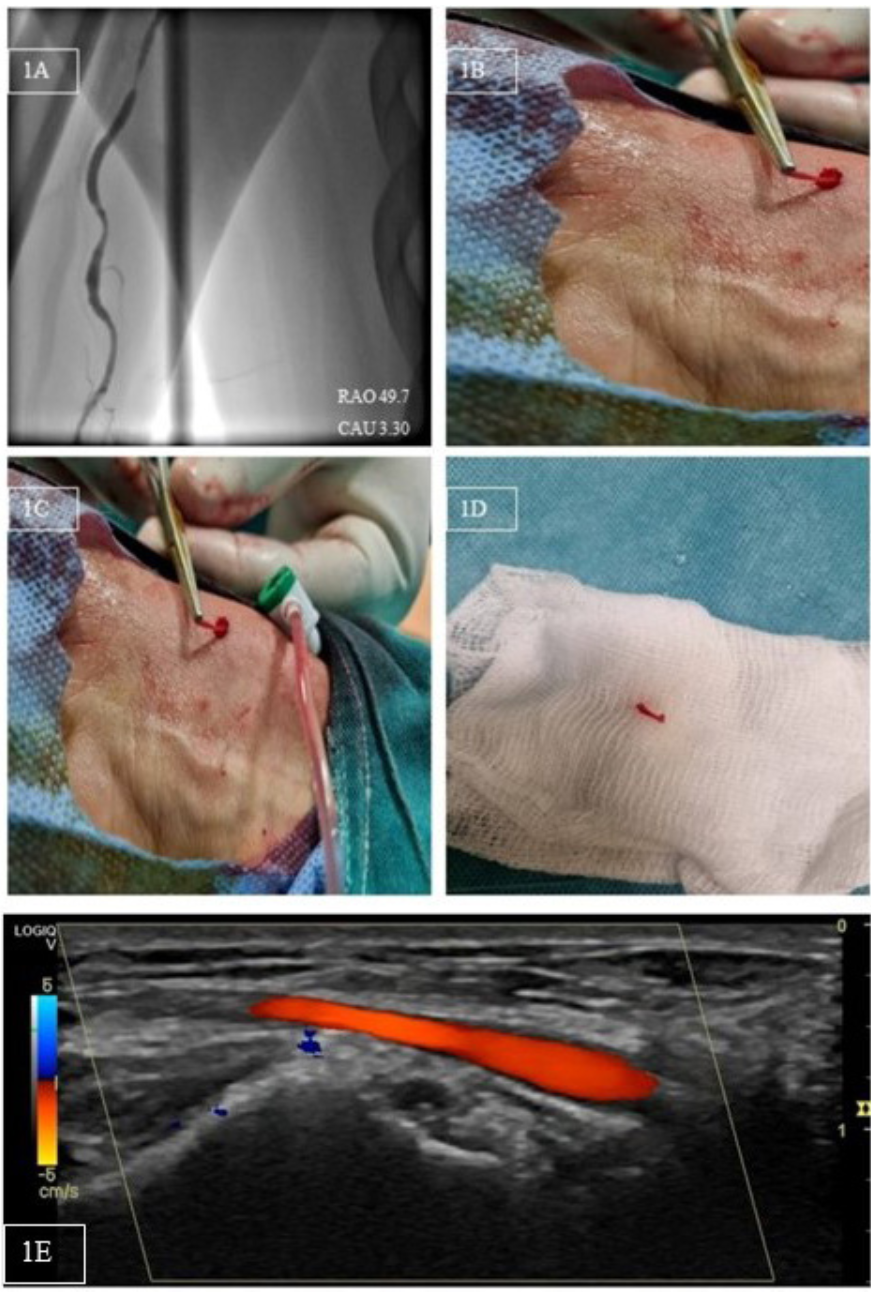

In our patient, repeated administration of local anesthesia with subcutaneous lidocaine and mild sedation with 1 mL of midazolam minimized nervousness, distress, and soreness perception, while serial delivery of subcutaneous and intra-arterial verapamil and nitroglycerin provoked local RA vasodilation tackling the spasm. The RA was then punctured proximally (Figure 1C). The avulsed RA fragment was excised (Figure 1D)and minimal bleeding required no further intervention. Radial pulse remained palpable, possibly because the adventitia remained intact or the avulsed RA fragment formed a minor RA branch. Histopathology was unavailable. CA was unremarkable (Video Series) and at 1-month follow-up, vascular ultrasound portrayed uncompromised blood flow (Figure 1E).